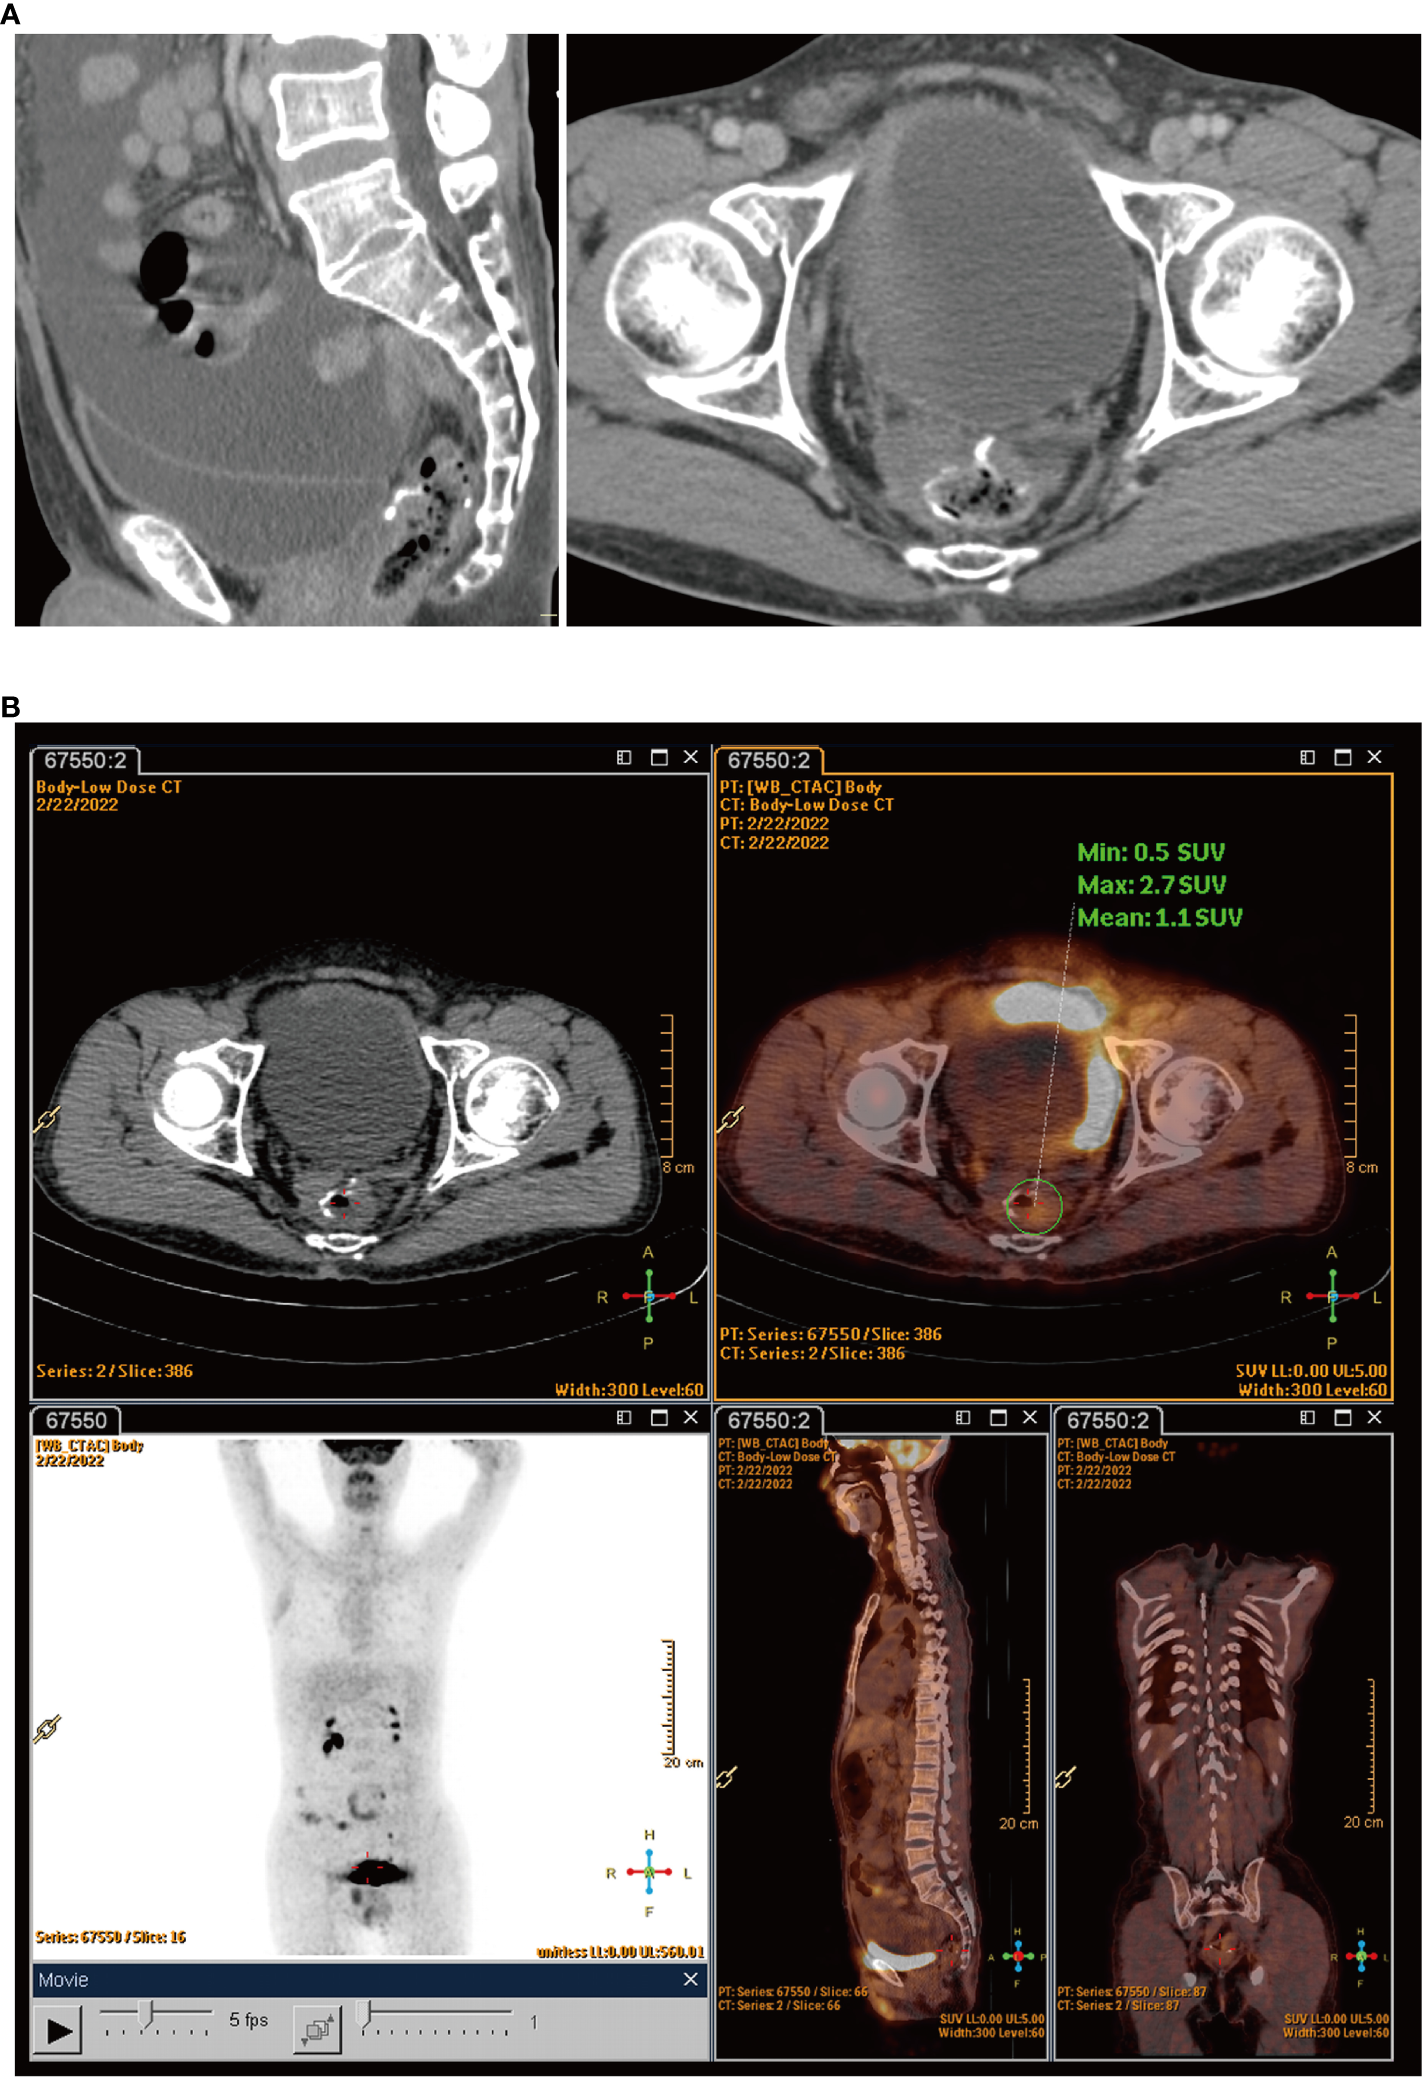

The patient felt an increase in abdominal circumference more than 2 months before the final chemotherapy. The enhanced CT rescan on Feb 18, 2022, suggested the following: 1) a circular line-like high-density shadow in the upper middle section, which was considered as a postoperative change; 2) a large amount of fluid in the abdominal cavity, which was new with a slightly thickened peritoneum compared with the old film from June 13, 2021; and 3) an increase in the splenic volume (SV) (Figure 3A). The positron emission tomography–computed tomography (PET-CT) on February 22, 2022, suggested: 1) thickening of the intestinal wall in the anastomosis area with surrounding soft tissue density shadow and a mildly increased metabolic activity in part of the intestinal wall, which was considered as a possibility of postoperative inflammatory lesions, and 2) an uneven thickening of the peritoneum, omentum, and mesentery, with peritoneal and pelvic fluid. Although metabolic activity was not increased significantly, metastasis could not be excluded (Figure 3B). The cancer spectrum on February 29, 2022, suggested CA19–9 of 4.3 kU/L, which was normal.

Figure 3

(A) Rescan of enhanced CT found a large amount of fluid in the abdominal cavity. (B) PET-CT scans showed uneven thickening of the peritoneum, omentum, and mesentery.